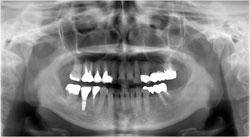

インプラントの埋入と親知らずの再植を行いました。